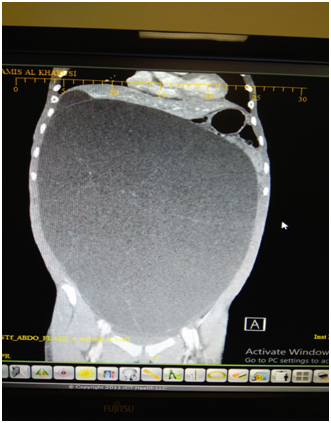

The liver, omentum and retro peritoneum were all normal. A thorough peritoneal lavage was done before closure, taking care to send the lavage returns for cytology- that was later reported as normal, with no malignant cells. Patient made an uneventful recovery and was discharged on the 3rd day. We received the final histology as follows. The cyst shows features of a Mucinous Cyst adenoma with Borderline Malignancy. No evidence invasion of the wall and no tumor of the external surface. Tubes showed evidence of salpingitis isthmica nodosa. FIGO classification Stage 1A (Figure 4).

Figure 4 Histology low and high power field showing papillaroid mucosa lined by mucinous lining epithelium which show stratification and atypia.